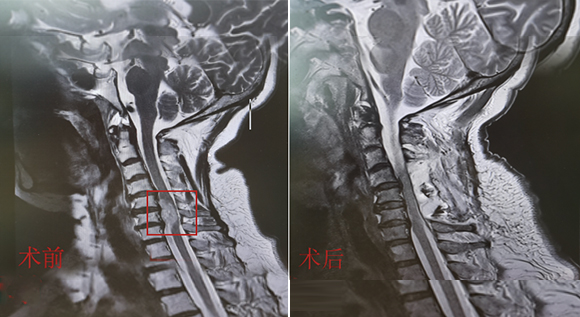

脊柱脊髓神經(jīng)微創(chuàng)中心以微創(chuàng)技術(shù)為引領(lǐng),以功能恢復(fù)為目標(biāo),主要治療脊柱外傷、腫瘤、退行性病變、脊柱畸形等疾病。團(tuán)隊(duì)利用神經(jīng)外科顯微技術(shù),結(jié)合神經(jīng)內(nèi)鏡微創(chuàng)技術(shù),對(duì)脊柱間盤變性疾病、頸腰椎管狹窄、頸腰椎間孔狹窄、頸腰椎間盤突出、頸腰椎體不穩(wěn)、脊柱骨折、寰樞椎脫位、脊柱腫瘤、椎管內(nèi)腫瘤、脊髓損傷、脊髓空洞、脊髓栓系等疾病進(jìn)行高效、特色手術(shù)治療,如顱頸交界區(qū)畸形寰枕減壓內(nèi)固定術(shù)、脊柱腫瘤全脊椎切除內(nèi)固定術(shù)、微創(chuàng)椎管內(nèi)腫瘤切除術(shù)、微創(chuàng)脊柱旁腫瘤切除術(shù)、寰樞椎脫位椎間融合內(nèi)固定術(shù)、脊柱骨折微創(chuàng)經(jīng)皮椎弓根釘內(nèi)固定術(shù)、經(jīng)椎間孔椎間融合內(nèi)固定術(shù)(MIS—TLIF)等,最大程度降低脊柱脊髓手術(shù)創(chuàng)傷,具有創(chuàng)傷小、輸血少、恢復(fù)快、口碑好,出院早等優(yōu)勢(shì)。